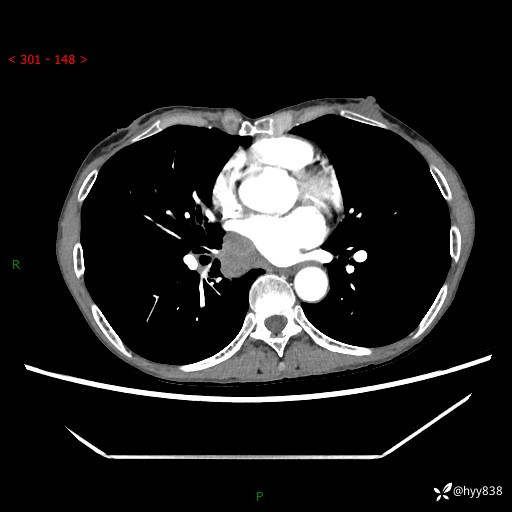

【患者信息】:69岁/女

【主诉】:发现肺占位3天余

【现病史及既往史】:患者3天余前因既往肺气肿复查胸部CT发现“右肺下叶结节、双肺多发结节、双肺门及纵膈淋巴结增大”,平素偶有咳白色粘液痰,下肢乏力,无明显低热、盗汗、咯血、胸痛、喘气等不适,今为求明显结节性质遂来我院门诊就诊,门诊以“孤立性肺结节”收治入院。 起病以来,患者精神饮食睡眠一般,大小便正常,体力无明细变化,体重近年来较前下降。

【检查】:胸部CT增强